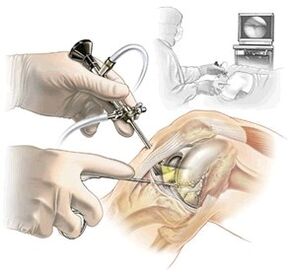

- Arthroskopie: Wird bei Meniskusverletzungen durchgeführt, die Schmerzen im Knie von innen verursachen. Diese Methode wird nicht nur zur Diagnose, sondern auch während der Behandlung durchgeführt;